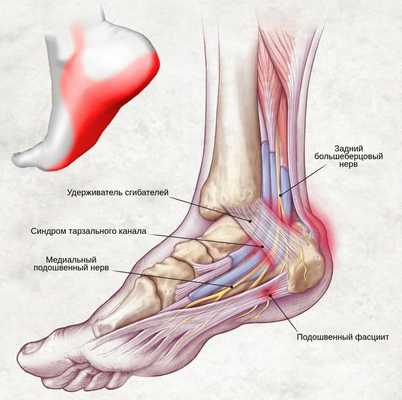

Синдром тарзального (предплюсневого) канала — это периферическая мононевропатия нижней конечности, которая возникает в результате сдавления большеберцового нерва, проявляющаяся болью в области голеностопного сустава по внутренней стороне стопы.

На уровне голеностопного сустава большеберцовый нерв проходит через жёсткий остеофиброзный туннель — тарзальный канал. [1] Это пространство спереди ограничено большеберцовой костью, а снаружи — задним отростком таранной кости и пяточной костью, а также удерживателем сгибателей (сухожилий).

Проходящий по поверхностям таранной и пяточной костей (в задней части лодыжки), канал предплюсны ограничивается удерживателем сухожилий-сгибателей. Постоянное раздражение находящегося в канале нерва вызывает стопное онемение и, соответственно, боль в данной области.

С точки зрения анатомии, канал предплюсны представляет собой пространство, где размещены сухожилия сгибателей пальцев (в том числе и первого), а также большеберцовые нерв и артерия. В свою очередь, большеберцовый нерв подразделяется на латеральный, пяточный и медиальный нервы.

Рис 1. Анатомические особенности канала предплюсны.

Удерживатель сгибателей представляет собой связку, которая, в норме, ограничивает канал предплюсны, а также удерживает находящиеся в нем анатомические элементы. Однако, при этом, именно связка может спровоцировать различного рода нарушения анатомической структуры голеностопа и стопы путем патологического сжимания содержимого канала.